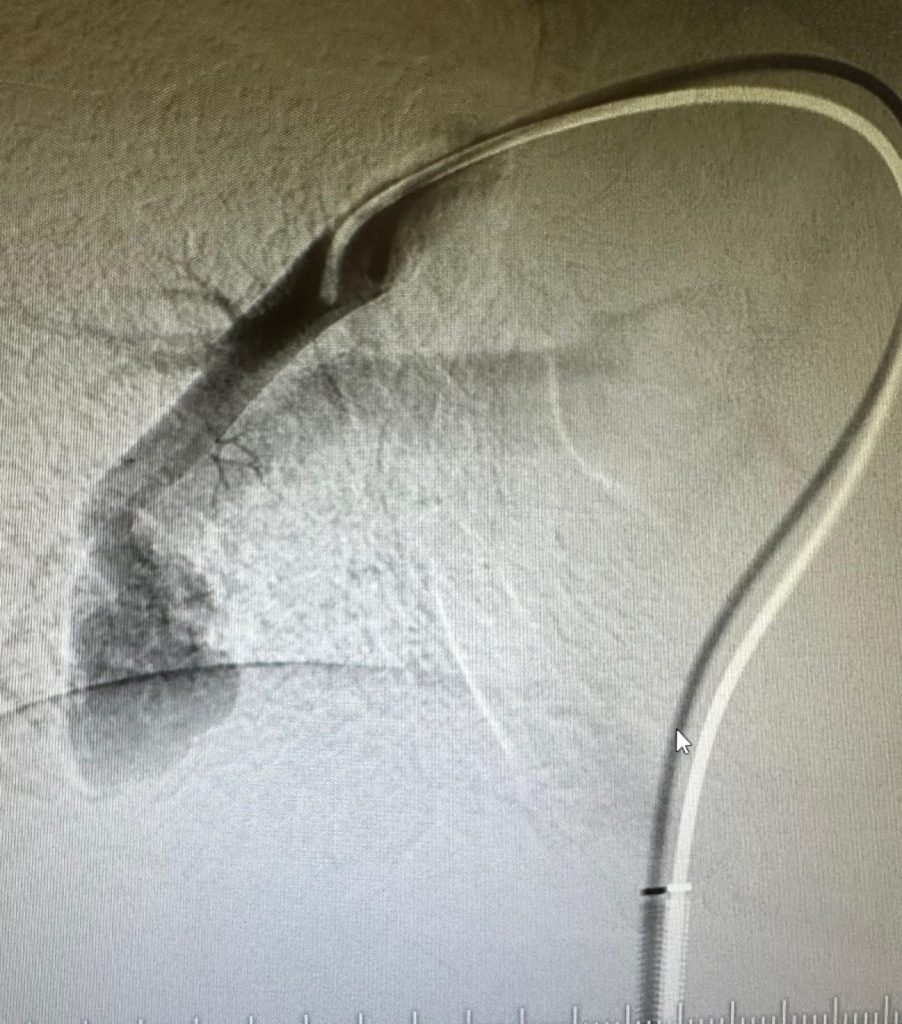

Samsun’da yaşayan Mustafa ve Tuba Çapkın çiftinin çocuklarını 9 yaşındaki Ahmet Utku Çapkın, yıllardır aşırı yorulma ve nefes darlığı şikayetiyle gittiği hastanelerden bronşit veya astım denilerek tedavi edilmeye çalışıldı. Her geçen gün yorulmaları artan ve artık arkadaşları oyun oynamakta zorluk çeken Ahmet Utku Çapkın, Samsun Kadın Doğum ve Çocuk Hastalıkları Hastanesi Çocuk Göğüs Hastalıklar Polikliniğine başvurdu. Burada Çocuk Göğüs Hastalıkları Uzmanı Dr. Fazılcan Zirek, çocuğun parmaklarındaki morluk ve bombeleşmeden yola çıkarak gerekli tetkiklerle tanıyı koydu. Çocuğun akciğerlerinde saptanılan yumak, endovasküler yolla (damar içerisinden) Samsun Eğitim ve Araştırma Hastanesi Girişimsel Radyoloji Uzmanı Doç. Dr. Hasan Gündoğdu ve Radyoloji Uzm. Dr. Öğr. Üyesi Mirsad Yalçınkaya tarafından tedavi edildi.

Tedavi ile ilgili bilgi veren Doç. Dr. Hasan Gündoğdu, “Böyle bir hastalığı hem saptamak hem de ilgili merkeze yönlendirmek gerçekten çok zor bir iştir. Dr. Fazıl Can hocamın hem hastalığı saptadı hem de ilgili merkeze yönlendirdi. Biz de girişimsel radyoloji ekibi olarak Dr. Mirsad hocamla birlikte hastamızın tedavisini en kısa zamanda gerçekleştirdik. Bizim açımızdan son derece güzel bir operasyon oldu. Bölgemizde ve hastanemizde ilk defa böyle bir operasyonu başarılı bir şekilde gerçekleştirdik. Çocuğumuzun bundan sonra diğer çocuklarla birlikte aynı şekilde oynayabilecek olması, semptomunun ortadan kalkması bizleri sevindirdi. Bu hastalarda eğer tedavi edilmezse ilerleyen yaşlarda kan oksijen değerinin düşük olmasıyla birlikte çocukluk çağından oynayamayacak, belirli aktiviteleri yerine getirilmeyecekti. Bu da çocukta ruhsal problemleri ortaya çıkarabilecekti. Ayrıca burada damar yumağının daha da büyümesi sonucu hastada akciğerde ciddi kanamalara sebebiyet verebilirdi. Daha büyük problemleri ortaya çıkarabilirdi” dedi.

Çocuk Göğüs Hastalıkları Uzmanı Fazılcan Zirek ise “Ahmet Utku, Çocuk Göğüs Hastalıklar Polikliniğe geçen ay başvurdu. Geldiğinde şikayeti parmaklarında ve dudaklarında olan morarmasıydı. Uzun süredir bu şikayeti varmış. Beraberinde ise halsizliği ve baş ağrısı varmış. Hastamızın muayenesinde el parmaklarındaki bombeleşmeyi gördük. Hem bu morar dediğimiz siyanoz durumu hem de parmaklardaki çomaklaşma durumu bizim açımızın oksijen seviyesinin düşmesini gösteriyor. Tetkiklerimizi yaptık. İlk muayenemizde satürasyonu 84 olarak gördük. Çocuk hastalarda 93 bekliyoruz. Öyle olunca bir dizi tetkiklerini yaptık. Tetkiklerini yaptığımızda normalde olmaması gereken damar bağlantısı gördük. Normalde atardamarla kan gittikten sonra temizlenir toplardamar ile tekrar vücuda geri döner. Bunları da kılcal dediğimiz filtre görevindeki damarlar yapar. Bizim hastamızda bu damar bağlantısında filtre yapı yoktu. Böyle olunca kan temizlenmeden, direk olarak vücuda gidiyordu. Bu da oksijen düşüklüğüne neden oluyordu. Tetkiklerimizi yaptık ve tanımızı koyduk. Girişimsel radyoloji ekibi ile birlikte müdahalesini yaptık. Bu hastalarda en sık müdahale yöntemi embolizasyon dediğimiz şantın kapatılması işlemidir. Bu hastalar çok nadir görülen hastalardır. Genellikle erişkin yaşta tanı koyulur ama çocuklarda da görebiliyoruz. Doğuştan olabiliyor. Tedavisini yaptık. Tedavi sonrasında satürasyonu düzeldi. Hastamızın şikayetleri de geriledi” diye konuştu.